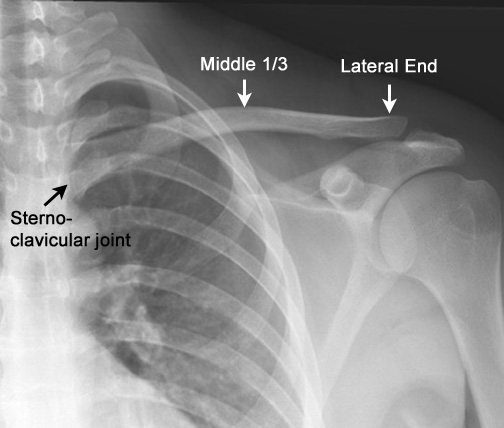

Identify parts of the clavicle. Click the image for labeling.